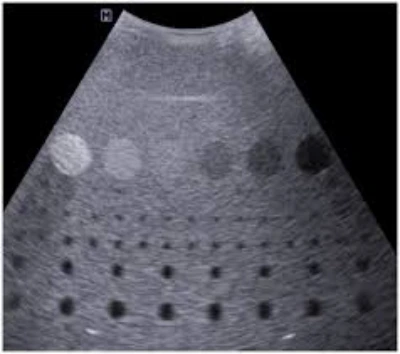

Aplicação em ultrassom

Inovações e Benefícios da aplicação em ultrassom na Medicina Moderna

A aplicação em ultrassom consiste no uso adequado do aparelho para exames de imagem médica, com técnica correta e calibração adequada . Essa prática promove precisão nas imagens, segurança para pacientes e eficiência nos procedimentos.